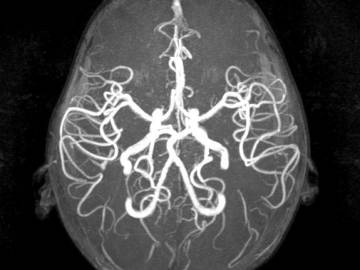

Компьютерная томография сосудов головного мозга

Компьютерная ангиография сосудов головного мозга – усовершенствованный метод диагностики, основанный на работе рентгеновских лучей. Она дает возможность получить детальные изображения артерий и вен головного мозга без стороннего вмешательства в организм пациента. Принцип визуализации сосудистого русла основывается на способности рентгеновских лучей с различной скоростью проходить сквозь ткани различной плотности. Для того, чтобы на КТ снимках врач мог качественно визуализировать сосуды, необходимо применение контрастного вещества на базе йода. Данная форма ангиографии дает очень точный результат, но, как и любая форма рентгенологического обследования, сопряжена с лучевой нагрузкой на организм. В среднем доза облучения за один сеанс сканирования составляет 3-5 мЗв.

Как правило, КТ сосудов головного мозга применяют в следующих случаях:

• есть подозрения на инсульт;

• поиск аневризмы головного мозга;

• диагностика атеросклероза;

• оценка степени мальформаций и окклюзий.